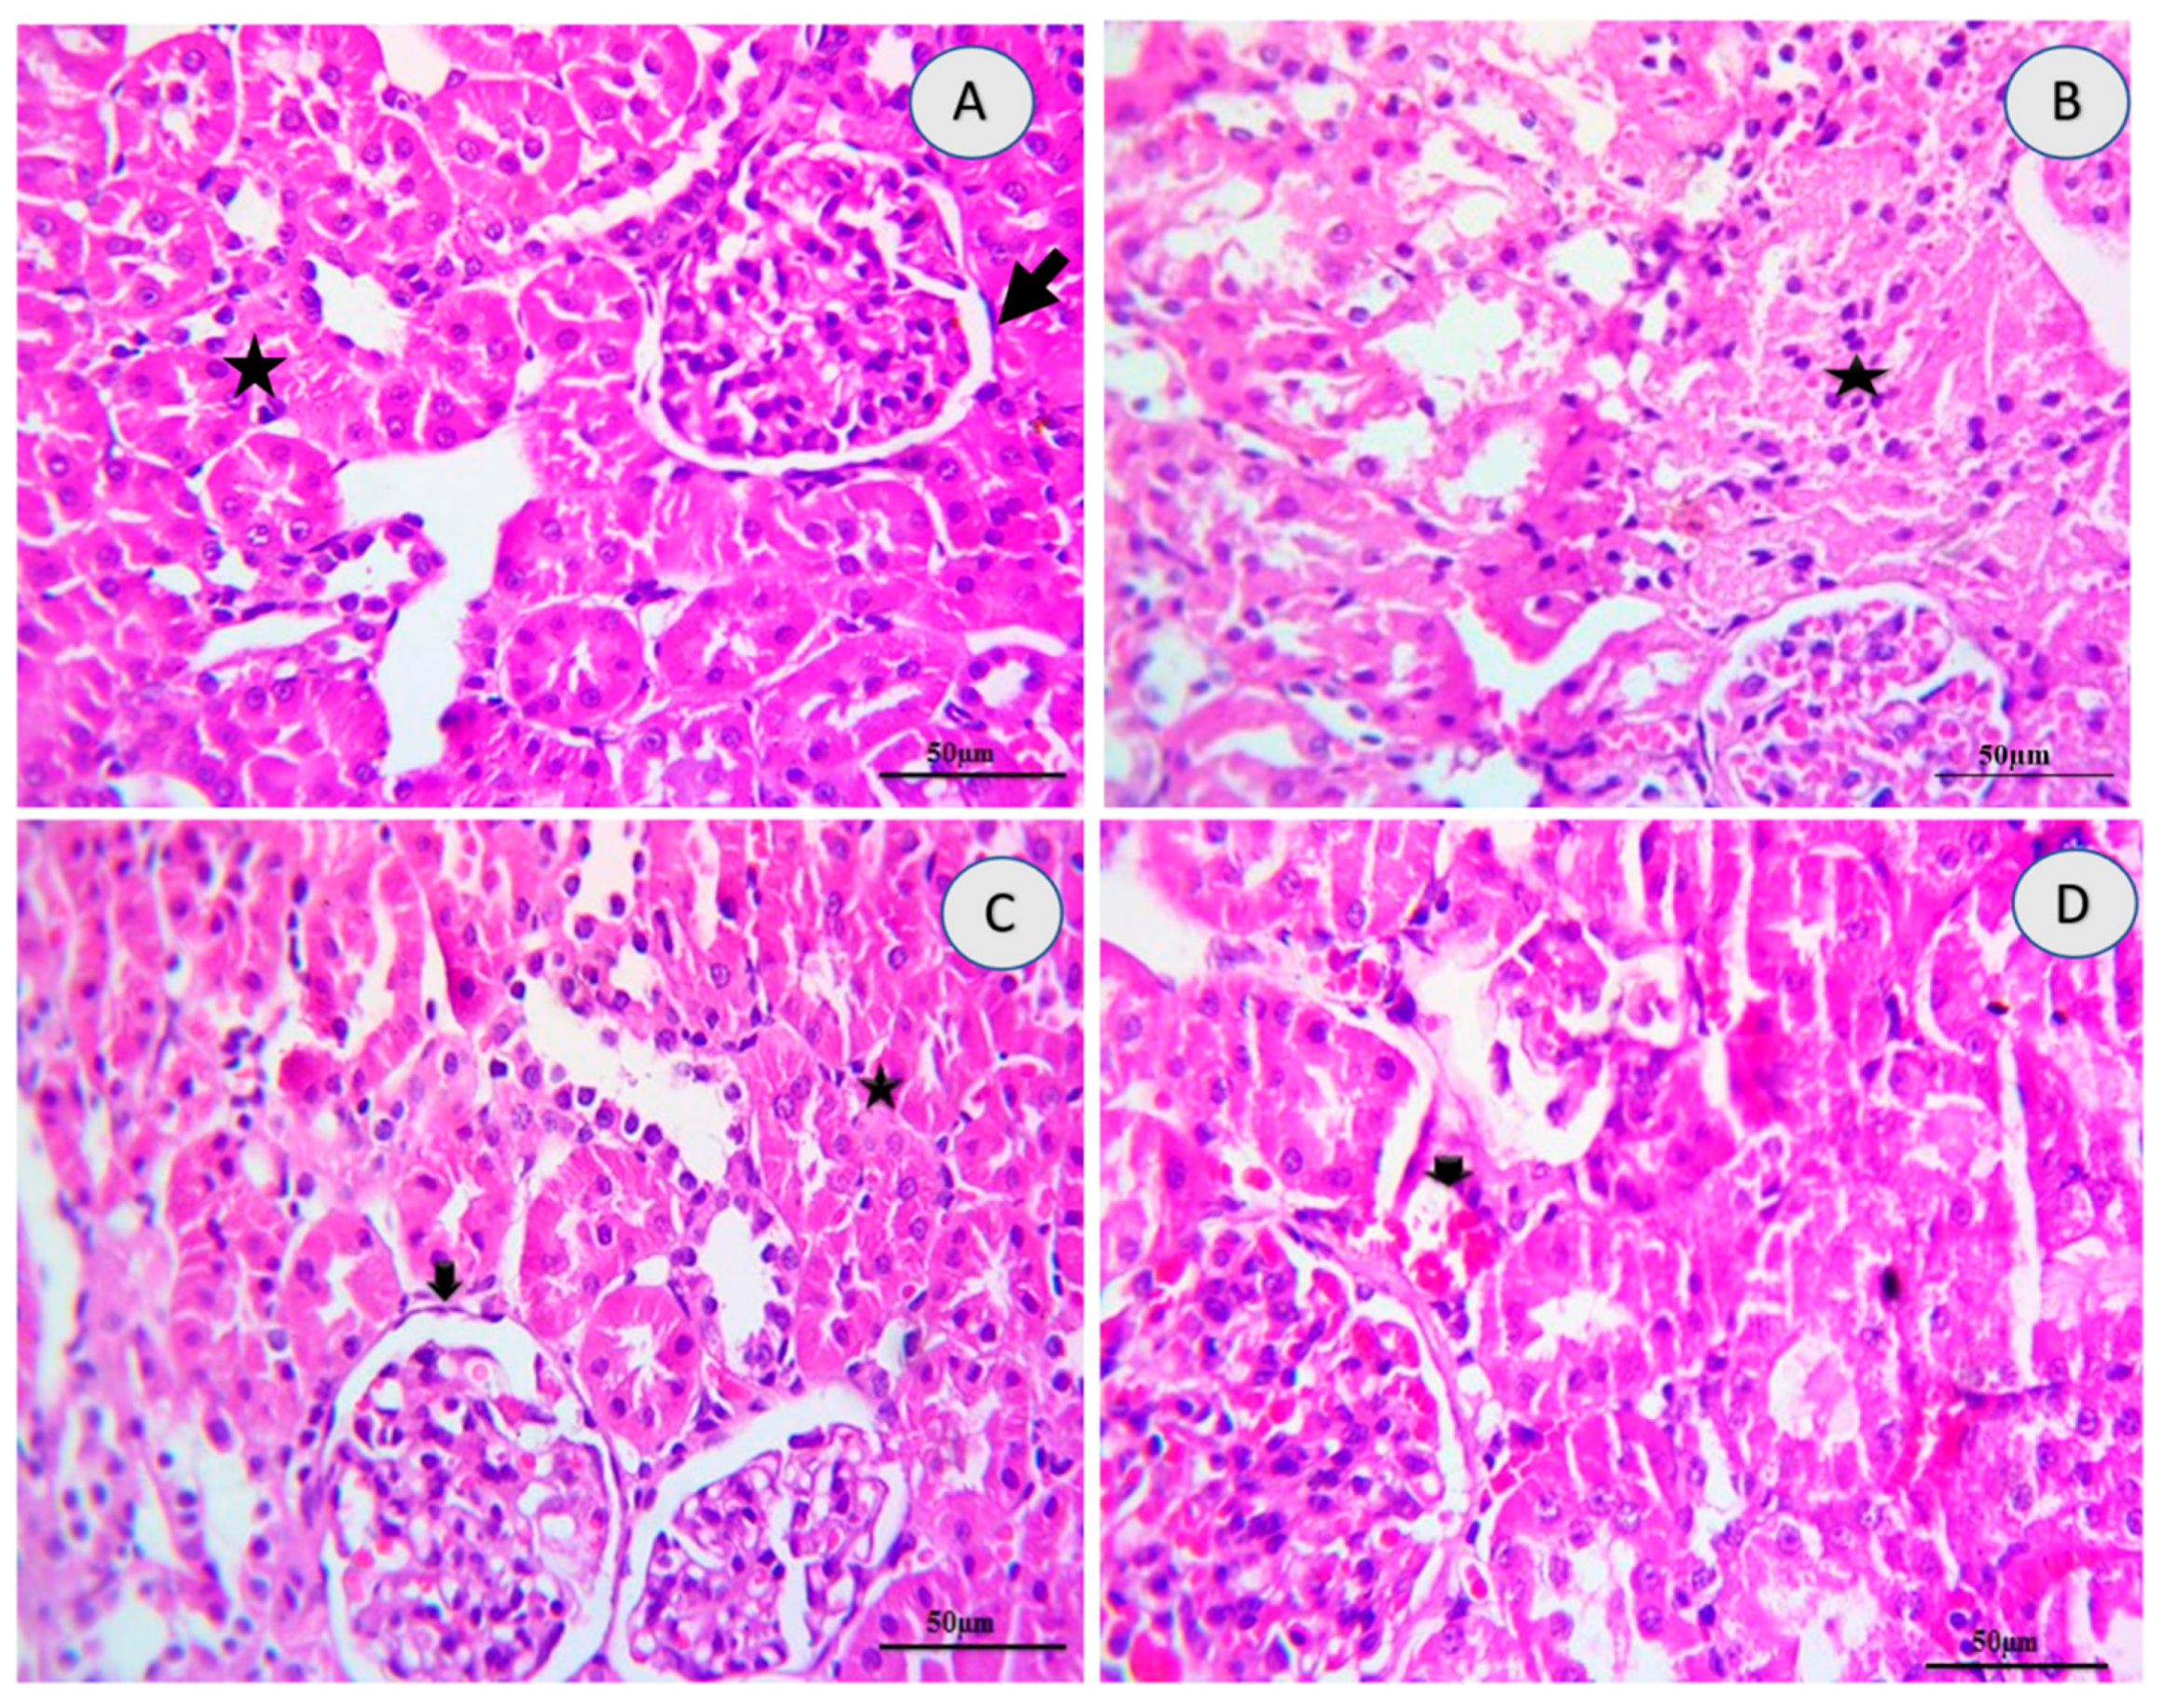

2.5. Renal Histology

| Lesions | Control | 10-DHGD | Tramadol | Tramadol+10-DHGD |

|---|---|---|---|---|

| Inflammation (nephritis) | 0 | 0 | 2 | 0 |

| Necrosis/Degeneration | 0 | 0 | 3 | 1 |

| Hemorrhages | 0 | 0 | 3 | 1 |

| Cystic Dilatation | 0 | 0 | 1 | 0 |

| Fibrosis | 0 | 0 | 1 | 0 |

| Edema | 0 | 0 | 2 | 0 |

| Tubular Casts | 0 | 0 | 3 | 0 |